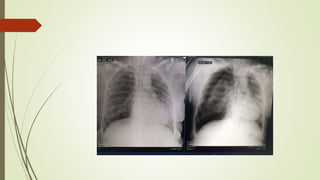

VAMOS

TREINAR?????